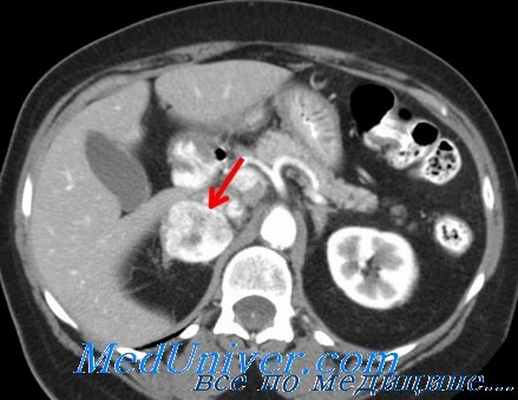

С целью тактической диагностики используют пневмосупраренорентгенографию, компьютерную томографию, магнитно-резонансную томографию, ангиографические исследования.

- компьютерная томография надпочечников;

- магнитно-резонансная томография надпочечников;

При аномальных результатах скрининговых тестов обычно используют визуализирующие методы с целью определить локализацию опухоли. Проводят КТ и МРТ грудной и брюшной полости с контрастом и без него. При использовании изотонических контрастных сред нет необходимости в блокаде адренорецепторов. Также успешно используется ПЭТ с фтордезоксиглюкозой (ФДГ), особенно при исследовании больных с мутацией сукцинатдегидрогеназы, но доказано, что ПЭТ-исследование с галлием-68 является более полезным.